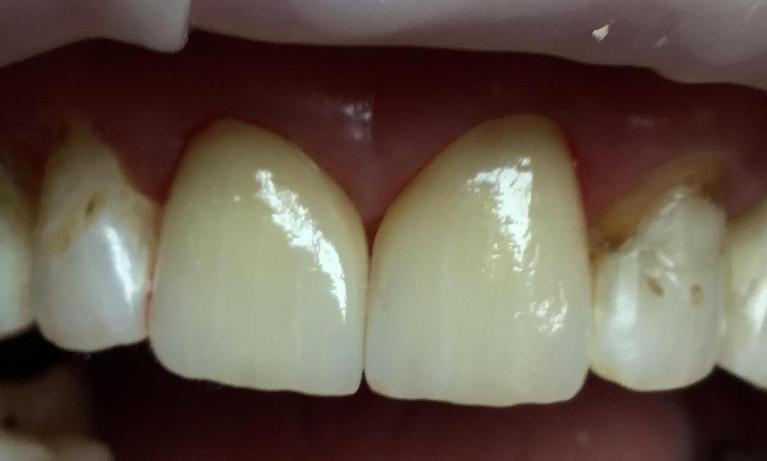

This patient had worn down her teeth over the years due to a bad bite. Dr. Farahani used Invisalign to move the teeth into a position where they could be restored and then placed 4 crowns top and bottom to give her back the length of her front teeth. This is a great example of the conservative restorative care provided at Harmony Dental Wellness to bring your mouth and body back into balance!